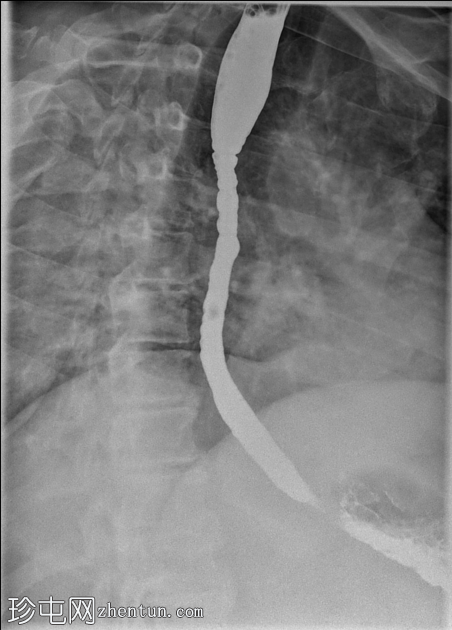

2.png

冠状位

透视食管造影显示食管内可见同心环状轻度狭窄,符合嗜酸性食管炎的影像学表现。近端食管轻度扩张,提示存在固定性狭窄。未见肿块或食管裂孔疝。

钡餐食管造影通常显示固定的同心环(“气管化”)、节段性狭窄或食管管径变细。